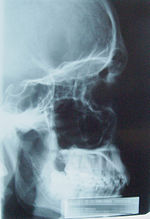

X-Ray Image of a male skull.

Since RĂśntgen's discovery that X-rays can identify bony structures, X-rays have been developed for their use in medical imaging. Radiology is a specialized field of medicine. Radiographers employ radiography and other techniques for diagnostic imaging. Indeed, this is probably the most common use of X-ray technology.

X-rays are especially useful in the detection of pathology of the skeletal system, but are also useful for detecting some disease processes in soft tissue. Some notable examples are the very common chest X-ray, which can be used to identify lung diseases such as pneumonia, lung cancer, or pulmonary edema, and the abdominal X-ray, which can detect ileus (blockage of the intestine), free air (from visceral perforations) and free fluid (in ascites). In some cases, the use of X-rays is debatable, such as gallstones (which are rarely radiopaque) or kidney stones (which are often visible, but not always). Also, traditional plain X-rays pose very little use in the imaging of soft tissues such as the brain or muscle. Imaging alternatives for soft tissues are computed axial tomography (CAT or CT scanning), magnetic resonance imaging (MRI) or ultrasound. Since 2005, X-rays are listed as a carcinogen by the U.S. government.